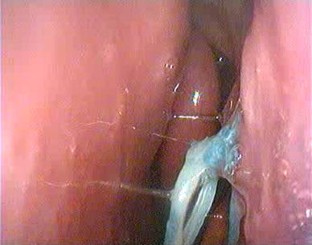

Endoscopic medial maxillectomy with preservation of inferior turbinate: how do we do it?

The aim of this study was to describe the endoscopic medial maxillectomy technique with preservation of the inferior turbinate in patients affected by maxillary sinonasal inverted papilloma. We retrospectively reviewed the clinical charts and surgical technique in six patients with paranasal sinus inverted papilloma. There were five males and one female, whose mean age at diagnosis was 60 years ranging between 57 and 65 years. No recurrences were diagnosed, and no nasal crusting was evidenced postoperatively. Nasal breathing was satisfying in all cases. Postoperative epistaxis was not observed, and none of the patients refereed to have epiphora after the surgery. This technique has been successfully performed, showing no recurrence to the present and allowing the preservation of a functional inferior turbinate.

Fig. 1

Fig. 2

Fig. 3

Fig. 4